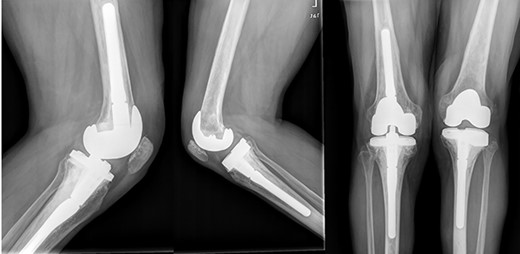

In the subsequent follow-up, pain progressively increased in the contralateral knee. Standing X-rays confirmed a severe deterioration of the right knee (Fig. 7). Given the bone defect and the consequent instability (Fig. 8), a CCK-type prosthesis was required, including medial femoral condyle blocks. The microbiological results were again negative, whereas the pathology results confirmed both severe osteoporosis and osteonecrosis.

Evolution of the right knee by standing radiographs during follow-up with progression toward joint space disappearance (Kellgren–Lawrence 4) in a severe varus deformity.

In the early postoperative period, no complications were detected, with pain decrease. After 4 years, the patient’s active ROM was 0–110° bilaterally, with no signs of radiological loosening (Fig. 9) and no pain, leading an unrestricted walking daily life without aids.

Both knees standing radiographs at 4-year follow-up with no signs of radiological loosening.